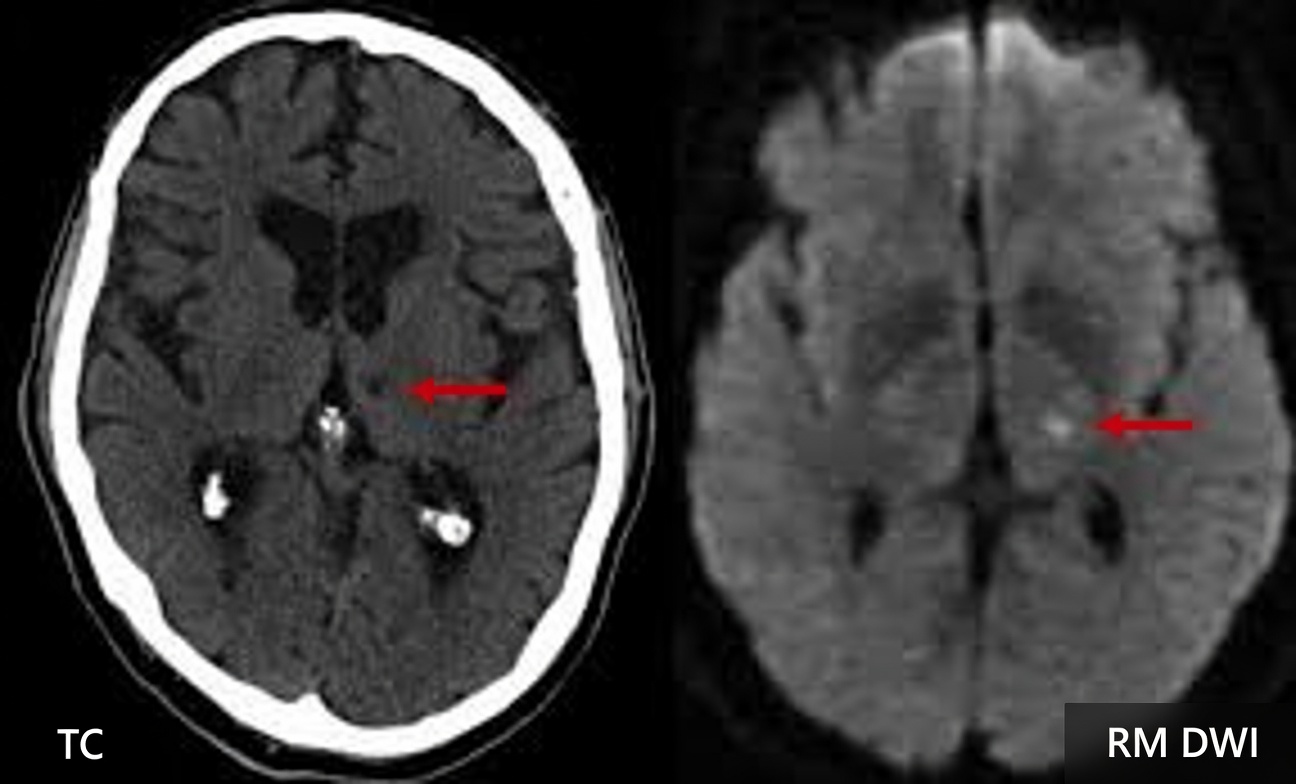

Os sinais de alerta de AVC lacunar surgem quando pequenas artérias nas regiões profundas do cérebro ficam obstruídas, formando minúsculas cavidades que lesionam áreas críticas como os núcleos da base e o tálamo. Muitos adultos acima dos 60 anos convivem com esses sinais por anos sem perceber, enquanto veem seu equilíbrio, atenção e foco diminuírem e culpam tudo por “lapsos da idade”.